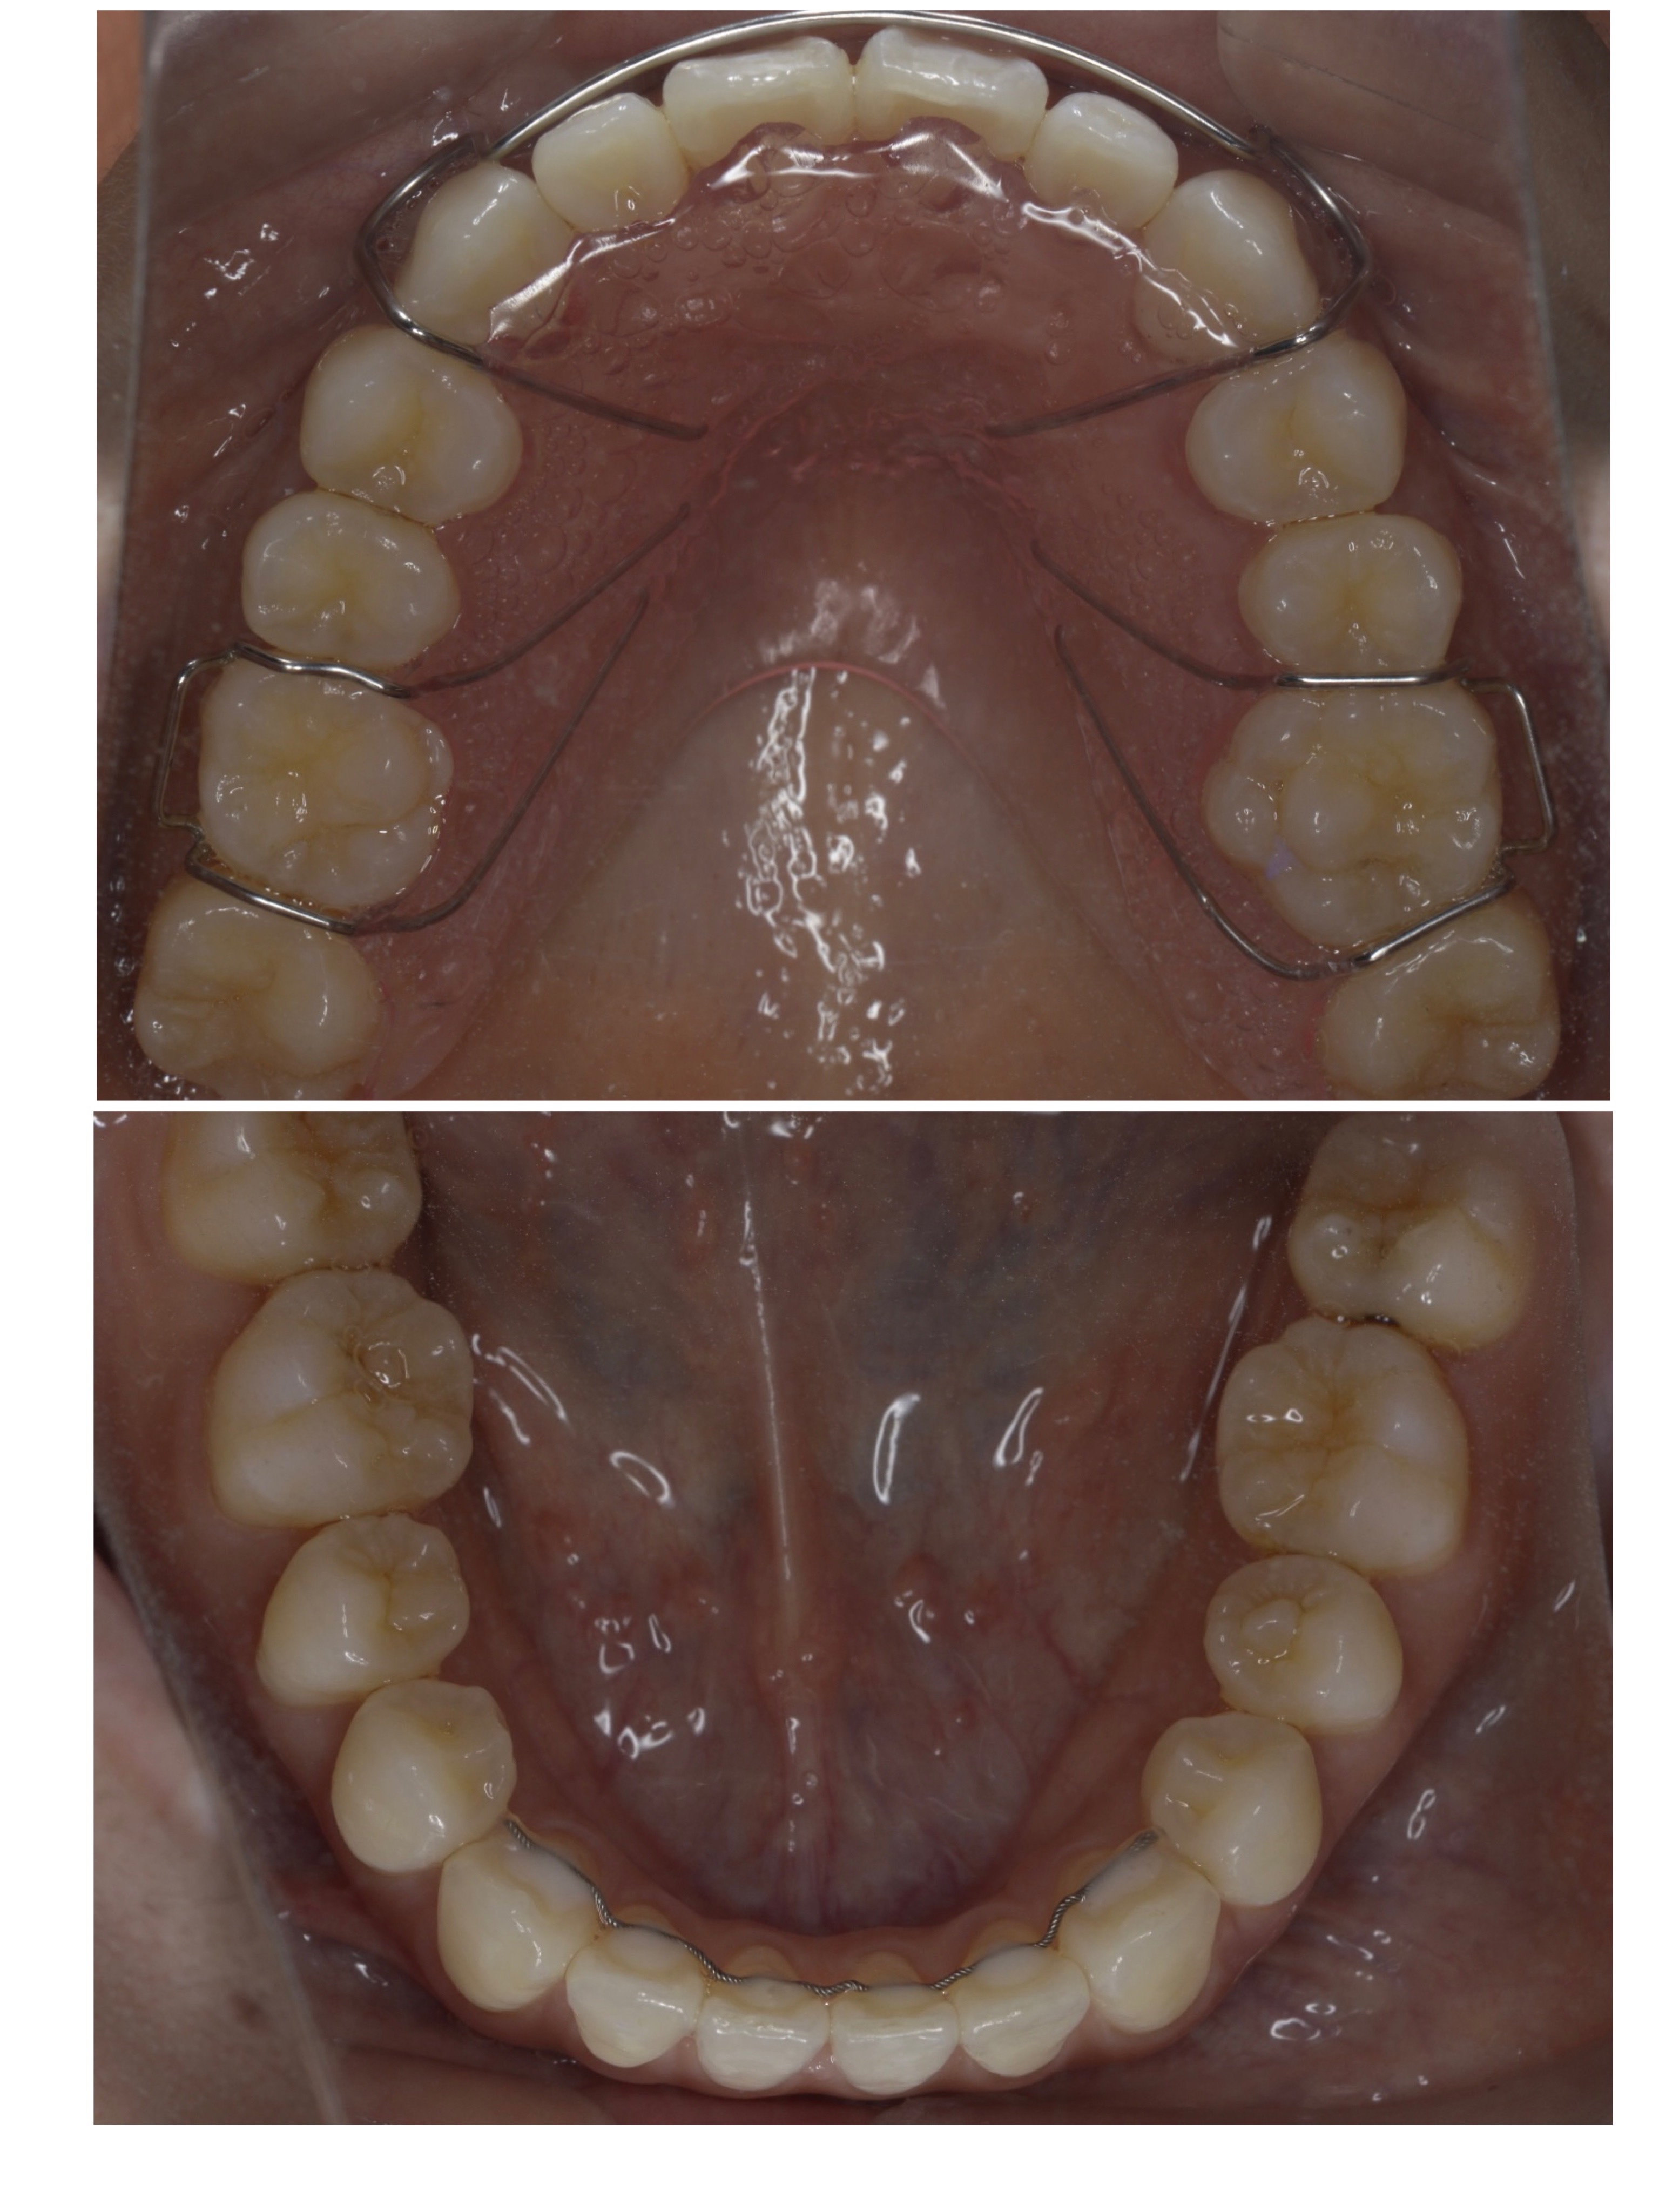

先日、当院に矯正治療に通われている患者様の

治療が終了しました!

約1年半頑張っていただきました!

2021/10/8~2023/3/17

30代女性